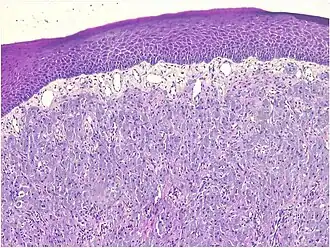

A low-power microscopic image reveals stratified squamous epithelium with a subepithelial proliferation of large polygonal cells arranged in nests and dense sheet [7]

Histopathologically, congenital epulis is usually characterized by the presence of big, rounded cells that fill the mucosa's lamina propria and have round to oval nuclei and an abundance of eosinophilic cytoplasm.[10] A thin layer of connective tissue separated the surface layer of cells from the growing new cells. Numerous histological traits, such as a fibrous and granulomatous appearance, have been reported in recent research.[10]

Microscopically, congenital epulis is composed of:

• Sheets of proliferating polygonal to round cells with overlying thin squamous, eosinophilic, granular cytoplasm[12][13]

• Centrally located, round nuclei [7]

These histopathological features are essential in distinguishing congenital epulis from other gingival and soft tissue neoplasms.